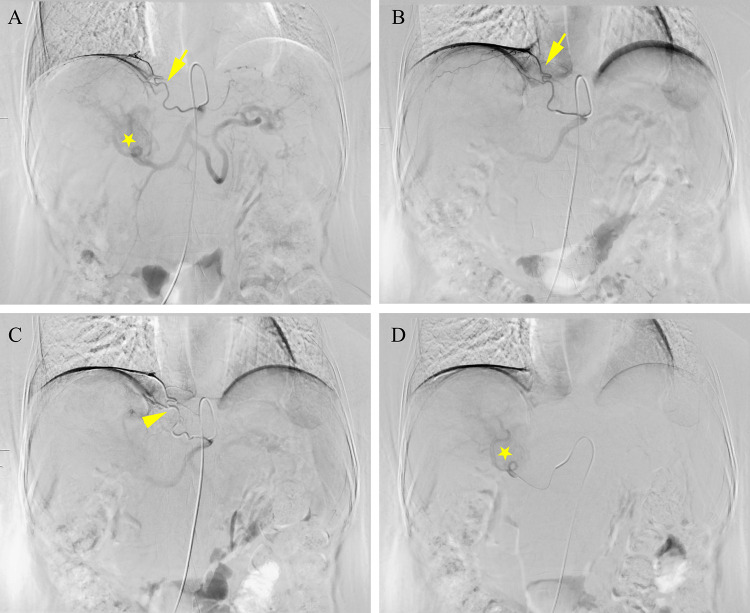

Objective: This retrospective study was conducted to evaluate the effectiveness and safety of a new combination therapy of the multi-level comprehensive collateral artery embolism (CAE) sequential hepatic arterial infusion chemotherapy (HAIC), tyrosine kinase inhibitors (TKI) and immune checkpoint inhibitors (ICI) for unresectable huge hepatocellular carcinoma (>10cm) patients.

Methods: A propensity score-matching (PSM) cohort study was conducted. The initial tumor response, treatment-related adverse events, and survival outcomes were compared. The Forestplot package was used to visualize and interpret forest plots of overall survival subgroup analyses. Univariate and multivariate analyses were conducted to explore the risk factors of overall survival.

Results: Thirty-one pairs of patients were evaluated after PSM. There were statistically significant differences in the initial tumor response and objective response rate (ORR) between the two groups (74.2% vs 48.4%, P=0.037). Compared with the "HAIC" group, the incidence of abdominal pain was higher in the "CAE+HAIC" group (71.0% vs 41.9%, P=0.021). The OS and progression-free survival (PFS) of the "CAE+HAIC" group were longer than those of the "HAIC" group (OS: HR=0.439, 95% CI: 0.199-0.970, P=0.042; PFS: HR=0.475; 95% CI: 0.252-0.895; P=0.021). The CAE (HR=0.403, 95% CI: 0.213-0.762; P=0.005), prealbumin levels <170 mg/L (HR=2.195, 95% CI: 1.226-3.929; P=0.008), and lactic dehydrogenase levels >245 U/L (HR=2.136, 95% CI: 1.215-3.757; P=0.008) were independent risk factors of OS.

Conclusions: The multi-level comprehensive CAE sequential HAIC, combined with TKI and ICI, can improve tumor response and prolong survival time in unresectable huge HCC patients while remaining safe and tolerable.